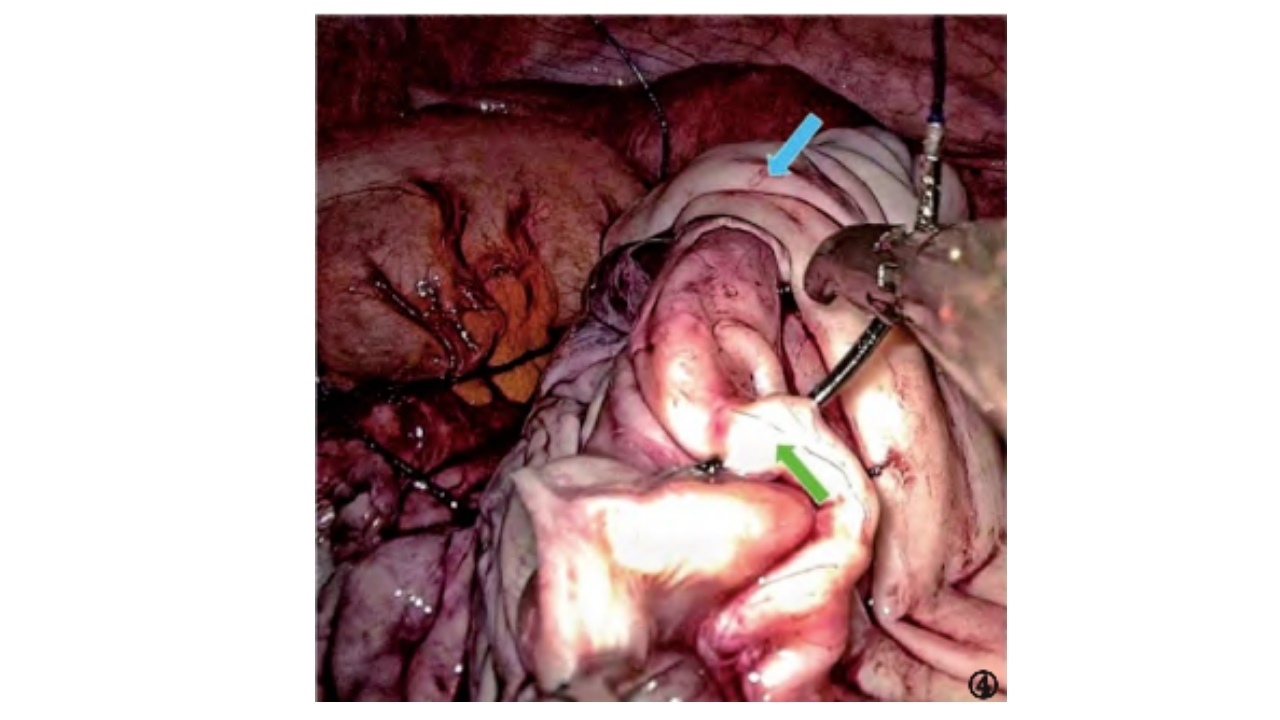

采用2/0-3/0可吸收缝线荷包缝合、连续缝合或“8”字兜底缝合,也可采用2/0倒刺线连续缝合。按照自固有韧带侧至骨盆漏斗韧带方向先深后浅的原则缝合卵巢创面,缝至骨盆漏斗韧带侧顶端后调转反向缝合,线尾需保留足够长度以备最后打结。

▪卵巢门附近以“8”字缝扎止血为宜,注意进针时不宜朝向卵巢门,应避免结扎卵巢动静脉影响卵巢血供,电凝止血不建议在该处使用,对卵巢功能影响较大。

▪若创面不深,可直接连续缝合;若创面较深,可先间断“8”字缝合基底部,再连续缝合卵巢皮质。